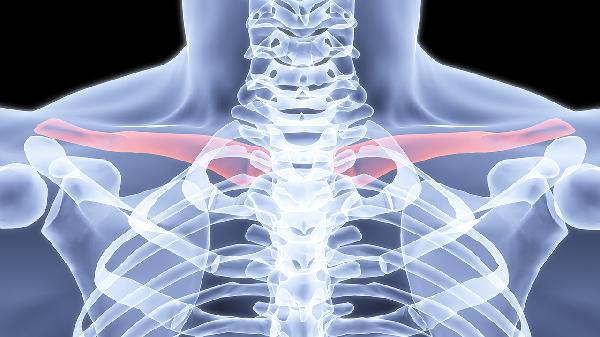

术后4周X线显示连续骨痂形成是安全活动的关键指标。CT三维重建能更准确判断愈合情况。医生触诊确认骨折端无异常活动后,方可逐步进行梳洗动作,从低位扎马尾开始适应。